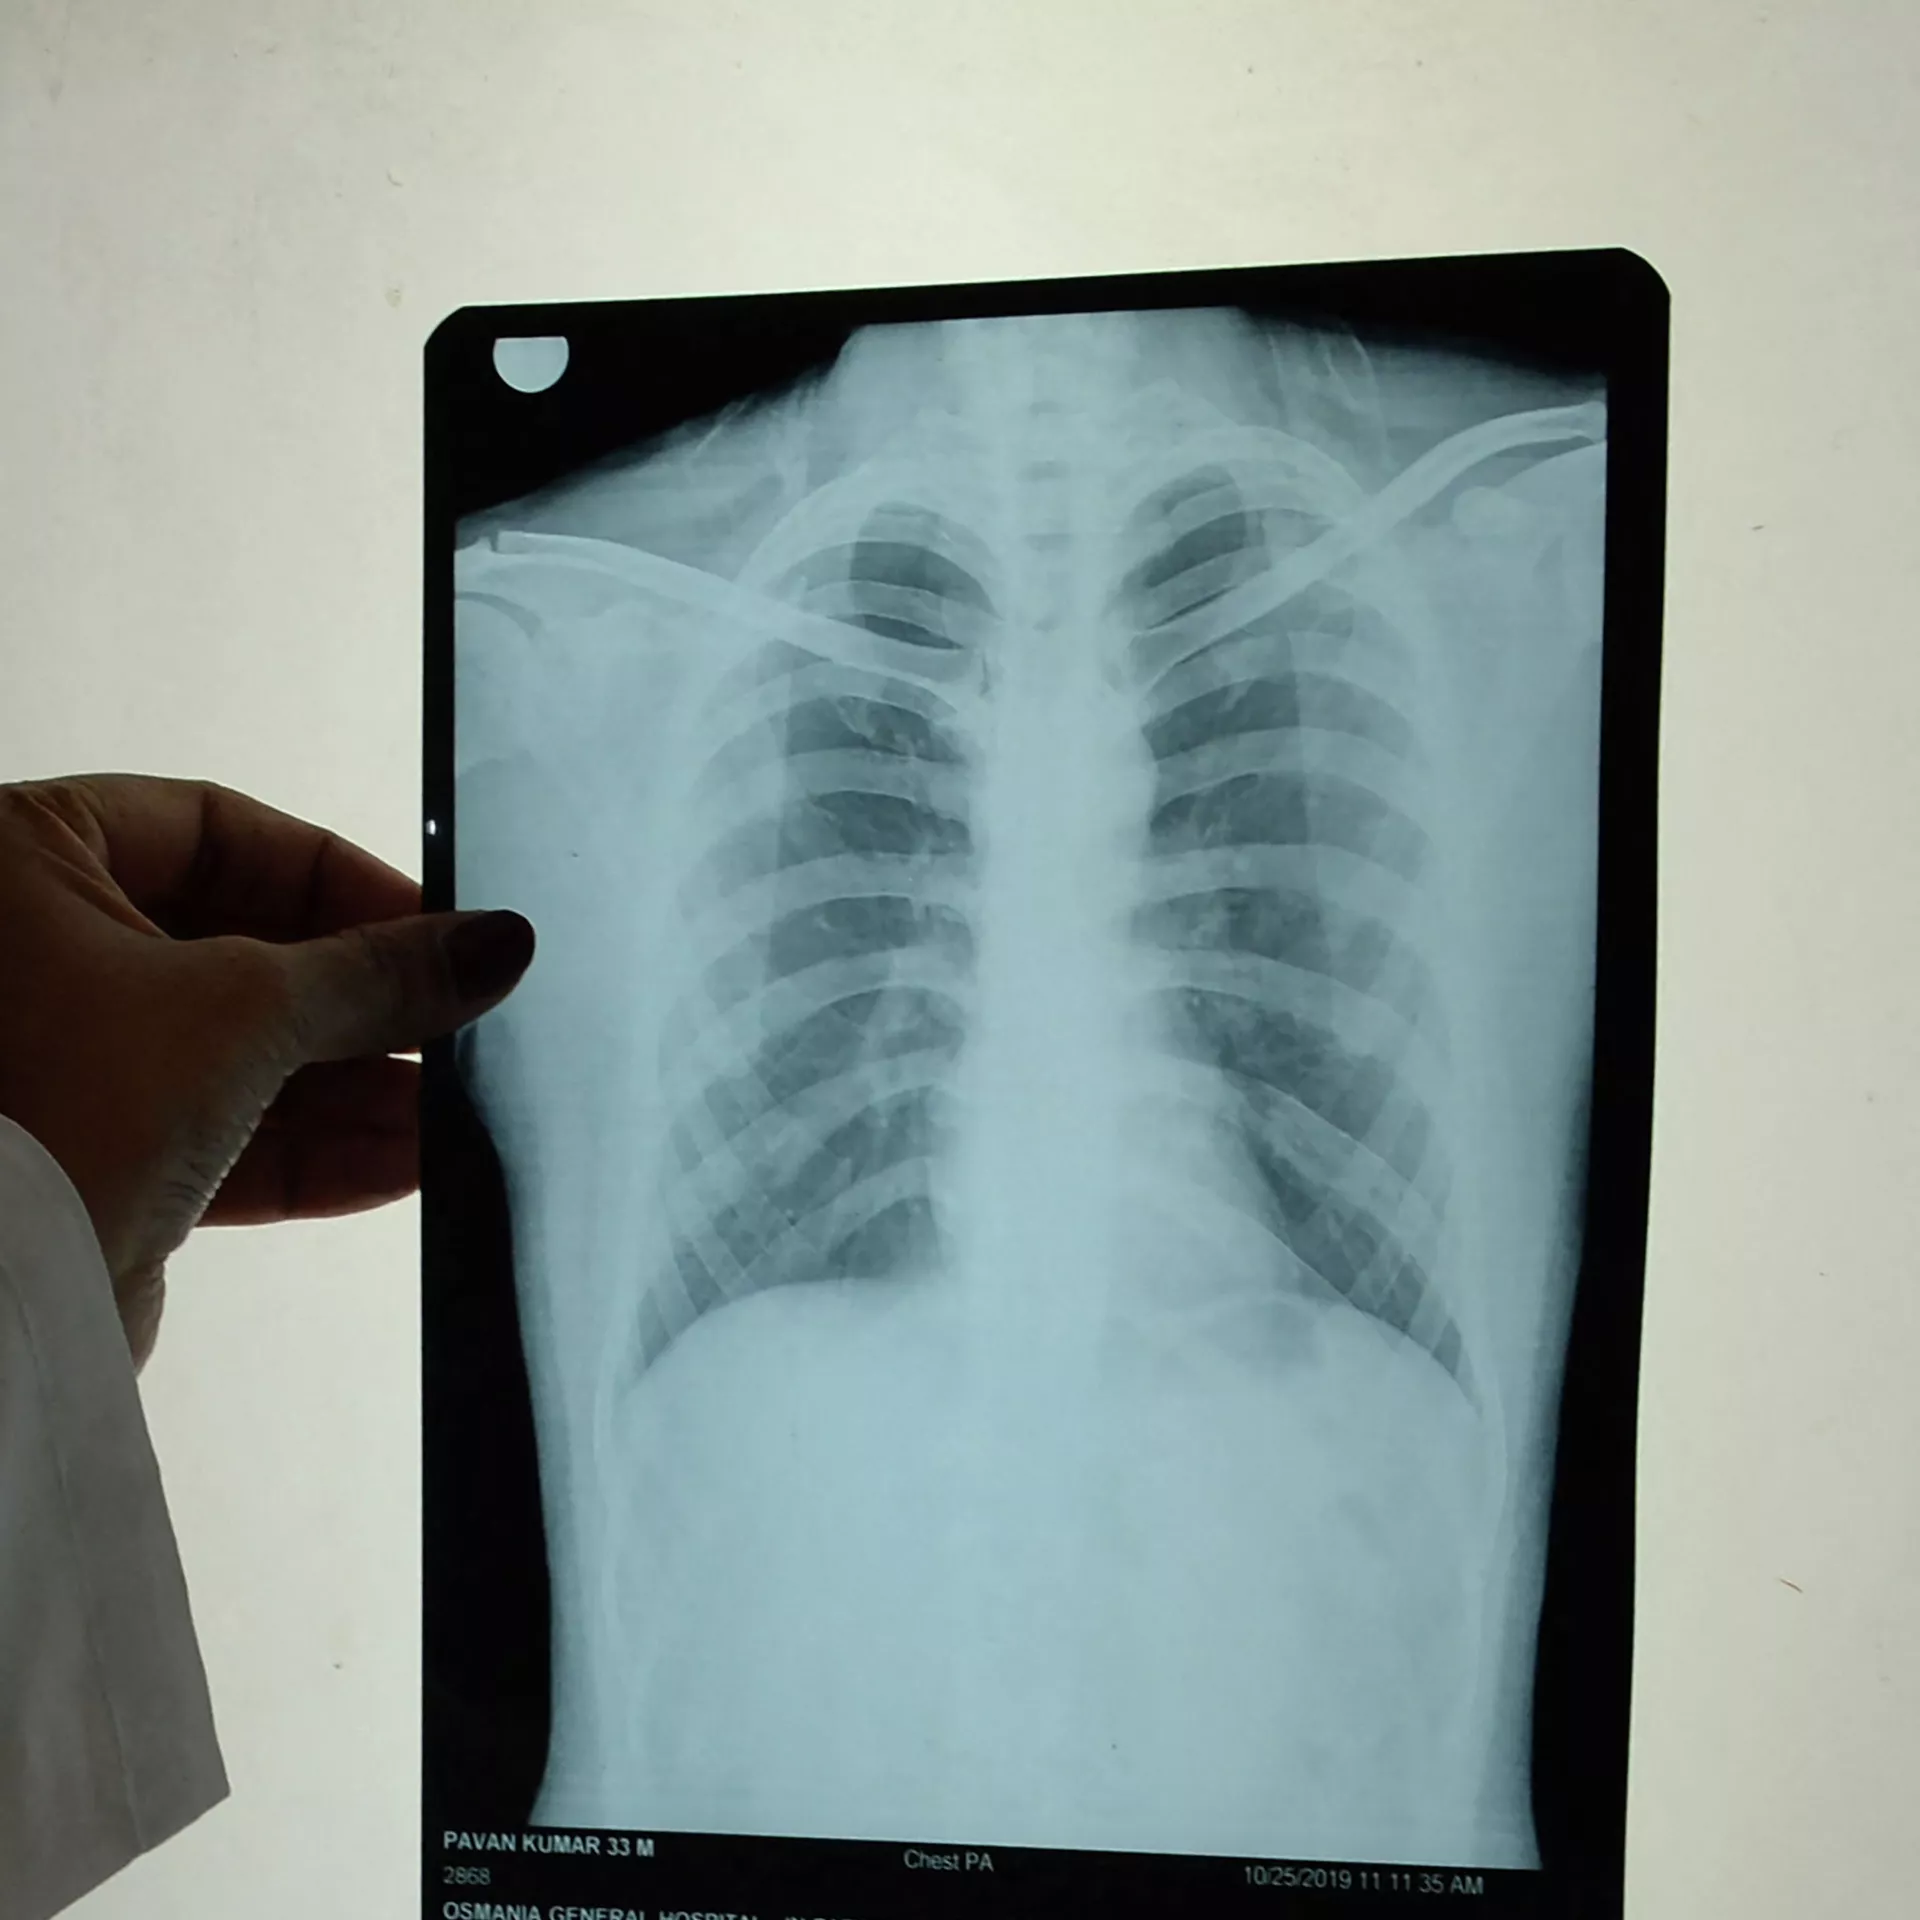

— Биринчи эле какырык тапшырат. Ал бардык аймакта бекер жасалат. Экинчиден, өпкөсүн рентгенге тарттырат. Ушул эки жолу менен эле аныктап коёт.